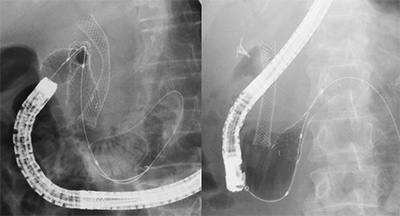

術後腸管に対するERCP

胃や胆管、膵臓の手術後の再建された腸管に対するERCP検査(術後再建腸管)もシングルバルーン小腸鏡や大腸内視鏡を用いて積極的に治療を行っております。

胃十二指腸ステント留置術

胃癌、十二指腸癌、膵胆道癌などが原因で、胃十二指腸閉塞症状をきたした場合に行います。膵癌では10-20%で十二指腸閉塞を発生すると言われています。従来の外科的バイパス手術に比較し、低侵襲な治療で閉塞症状を治療することが可能です。